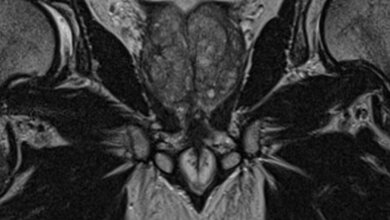

Auf dem ASTRO-Kongress in Boston wurde eine prospektive, multizentrische Studie zum CyberKnife System präsentiert, die gute Daten zur Tumorkontrolle bei Prostatakrebs-Patienten beinhaltete.

Accuray Incorporated gab heute die Ergebnisse einer prospektiven Studie zum CyberKnife® System bekannt: 97 Prozent der Prostatakrebs-Patienten mit niedrigem oder mittlerem Risiko erreichten fünf Jahre nach der stereotaktischen Strahlentherapie mit dem CyberKnife System eine exzellente Tumorkontrolle. Die Behandlung wurde sehr gut vertragen. Schwere Nebenwirkungen waren auch über fünf Jahre nach der Behandlung selten (weniger als zwei Prozent). Die Studie, an der 21 Zentren beteiligt waren, wurde gestern beim 58. Jahreskongress der American Society for Radiation Oncology (ASTRO) präsentiert und unter tausenden Abstracts als eine von 15 Studien zur Vorstellung auf der heutigen ASTRO-Pressekonferenz ausgewählt.